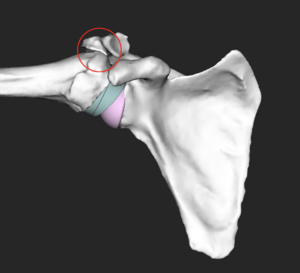

Tuberosity avulsions that require suture cerclage can bee observed (Figure).

A) Example of tuberosity avulsions (black arrows) requiring 3 suture cerclages. B) Tuberosity healing was observed at two-year follow-up.